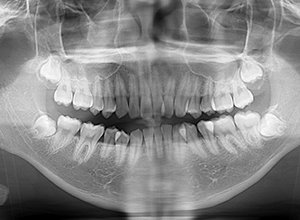

主訴 物が噛みづらい 診断名 下顎右側側切歯先天欠如を伴う過蓋咬合症例

口腔内所見 over jet 8.5mm、over bite 6.0mm、下顎前歯先天欠如、右側臼歯関係I級、左側II級(end on)、上顎歯列弓はオーボイド型なのに対して、下顎は狭窄歯列、叢生歯列弓を呈しており左側は鋏状咬合となっていた。

X-Ray所見

セファロ所見 下顎 頭はやや後方に位置しており、下顎枝の長さに対して骨体部は大きく、下顎角は開大しているためハイアングルを呈していた。中顔面部の高さは高く奥行きもあった。前後的にはII級の骨格形態を示していた。